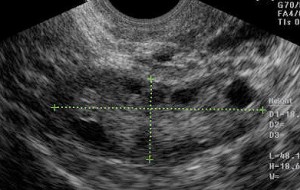

Ultrasound evaluation of the ovaries is another method for evaluating egg quality. The ovarian volume (> 3 cc) and the number of antral follicles (little black circles in the ovary which contain eggs, at least 3 – 4 in each ovary) give a good idea of the “ovarian age”.